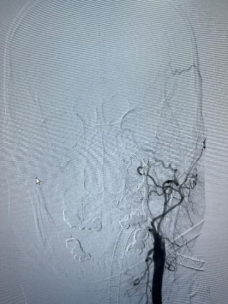

箭头所指为出血点

由于内镜下止血困难,考虑鼻咽癌治疗后并发颈内动脉爆裂综合征大出血,治疗团队立即将患者转入复合手术室。此时,神经外科脑血管病团队早已枕戈待旦,无缝衔接开始手术。面对患者大出血的危急情况,神经外科昝春树主治医师来不及穿戴铅衣,一头扎进抢救工作。股动脉穿刺,微导管、超滑导丝导引导管迅速超选至左侧颈内动脉等系列操作一气呵成。术中造影证实了左侧颈内动脉假性动脉瘤破裂出血,像一股洪流一样持续向外喷出。